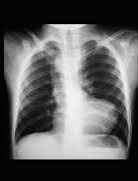

X-ray feature shown

Regarding the X-ray shown below